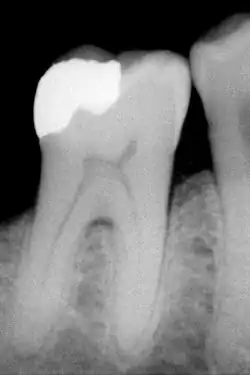

De eerste molaar is een molaar in de achterste delen van de mond, achter de premolaren (zie afbeelding). In een normale gebitssituatie is het de 6e tand vanaf het midden van de mond (centrale snijtanden). In een normaal volwassen gebit bevinden zich in totaal 4 eerste molaren, één in elk kwadrant. De eerste molaar breekt in de regel door op 6-jarige leeftijd.

Eerste molaren in de bovenkaak hebben vrijwel altijd drie wortels met elk een zenuwkanaal; mesiobuccaal, distobuccaal en palatinaal. Waarbij de mesiobuccale wortel twee kanalen kan bevatten. Ondermolaren hebben twee mesiale wortels en een distale wortel. In iets minder dan 60% van de gevallen bevat de distale wortel twee kanalen.